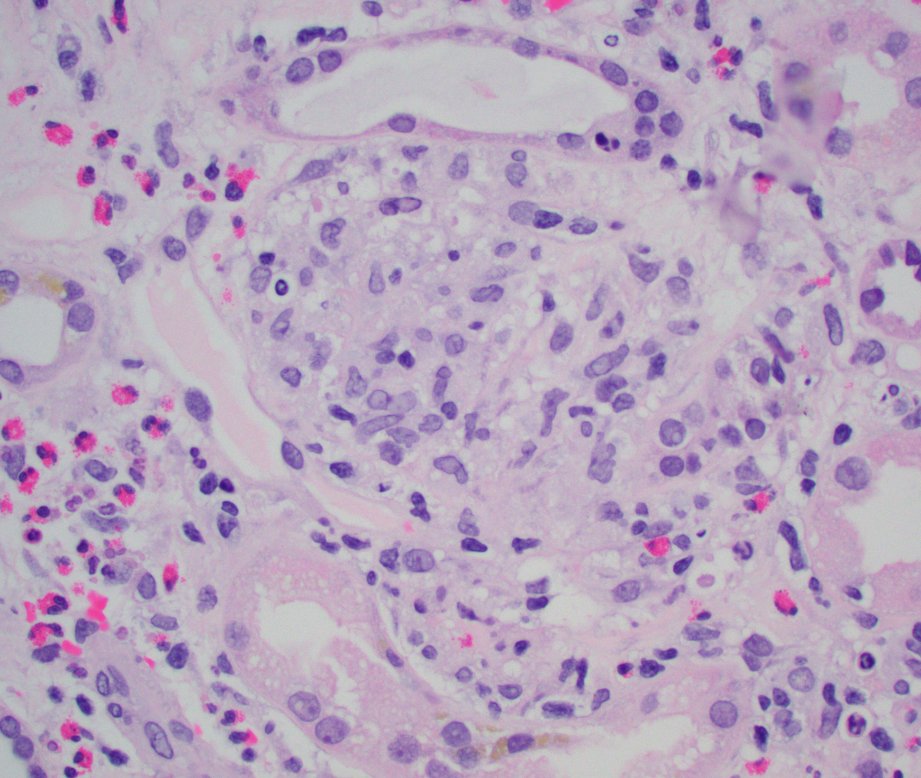

So many eosinophils in this case of tubulointerstitial nephritis secondary to recent antibiotic administration. Few tiny granulomas as well. Eos seen in EM as well. #renalpath #pathtwitter #nephrology